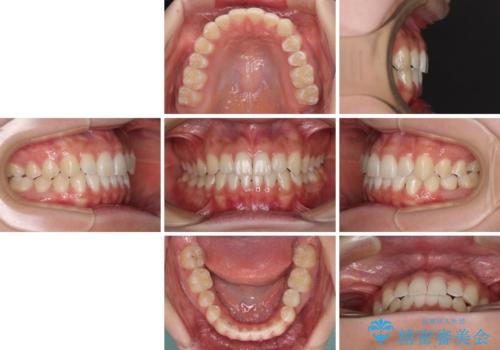

矯正治療が終わるタイミングに合わせてインプラントの埋入を行っていたので、矯正治療を終了すると同時にセラミック補綴治療を行えました。

短期間でしっかりと治療を終えることができました。